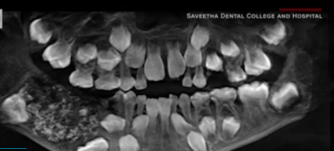

Мальчик был госпитализирован в прошлом месяце в южном городе Ченнаи из-за отека и боли около его коренных зубов в нижней челюсти. Когда врачи отсканировали и сделали рентген его рта, они обнаружили в нижней челюсти мешок, заполненный "ненормальными зубами".

"Всего было 526 зубов в диапазоне от 0,1 миллиметра (0,004 дюйма) до 15 миллиметров (0,6 дюйма). Даже у самого маленького куска была коронка, корень и эмалевое покрытие, что указывало на зуб", - сказал врач.

Врач сказал, что мальчик страдает очень редким заболеванием, которое называется составная одонтома. Причина возникновения болезни неизвестна, это может быть генетическое заболевание или факторы окружающей среды, такие как радиация.